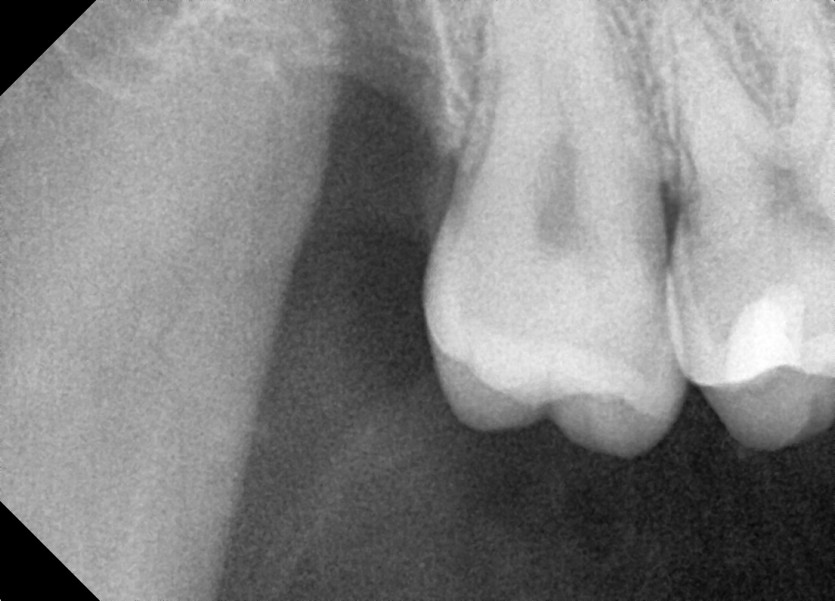

#18,28,38,48 사랑니 발치

구강 외과 전문의가 당일 발치했습니다.